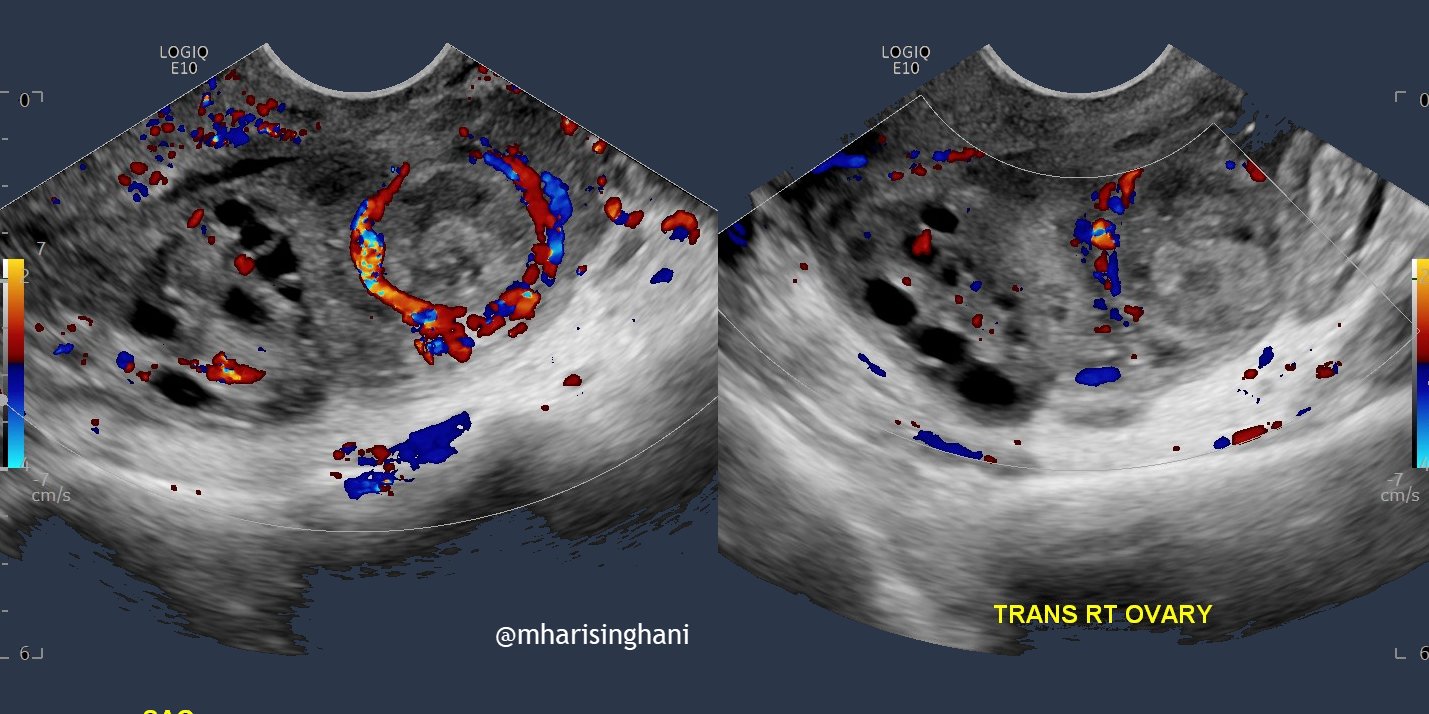

Fire Ring Pregnancy . When does the ring of fire happen? As you push, you will eventually get to a point where you can see the top of your baby’s head. While it’s one of the most intense. So what exactly is crowning? At first, you will see baby’s head just while actively pushing and. The ring of fire is pain caused by the baby’s head stretching the vaginal opening. What you should know about baby crowning. An absence of color doppler flow does not exclude an ectopic. You can help get through the ring of fire by choosing the best position for labor, using a perineal warm pack, or with perineal massage. If you’re expecting, you might have heard about the “ring of fire,” aka baby crowning, during labor. The ring of fire happens during the pushing phase of labor. Can be seen on color doppler in a tubal ectopic, but can also be seen in a corpus luteum. But more specifically, when baby’s head is crowning. When your baby’s head crowns, you will experience a burning or stinging sensation, often referred to. Crowning is often referred to as the “ring of fire” in the birthing process.

As you push, you will eventually get to a point where you can see the top of your baby’s head. Can be seen on color doppler in a tubal ectopic, but can also be seen in a corpus luteum. It’s when your baby’s head becomes visible in the birth canal after you’ve fully dilated. You can help get through the ring of fire by choosing the best position for labor, using a perineal warm pack, or with perineal massage. At first, you will see baby’s head just while actively pushing and. The term ring of fire is used to describe the sensation of intense burning or stinging that many women experience during the last stage of labor when the baby's head is crowning. When does the ring of fire happen? If you’re expecting, you might have heard about the “ring of fire,” aka baby crowning, during labor. But more specifically, when baby’s head is crowning. While it’s one of the most intense.